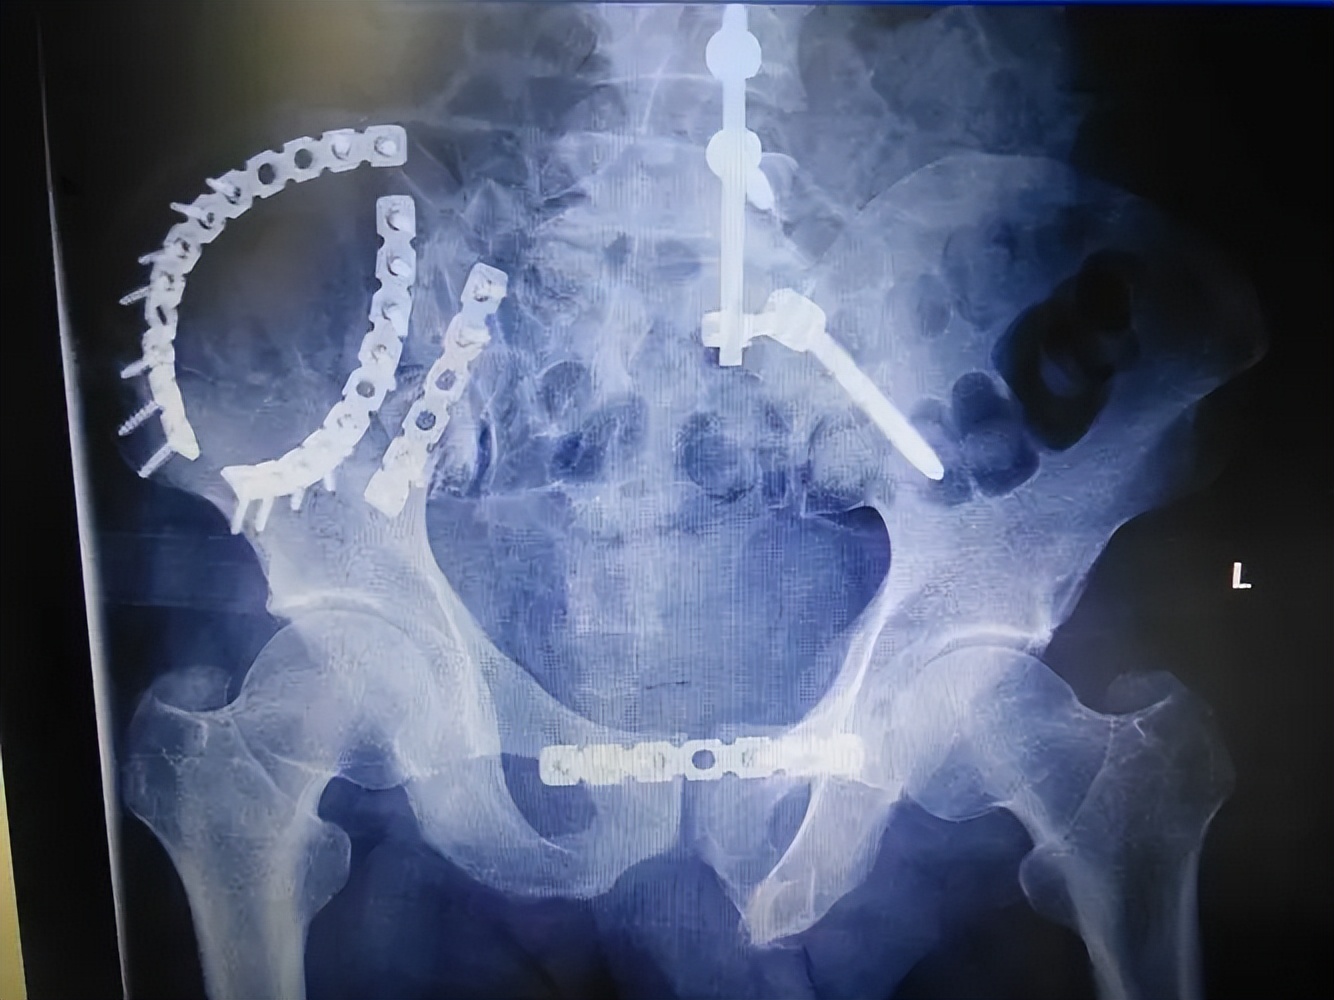

骨盆后环的稳定性可用骶髂关节前方双钢板来维持,前路双钢板固定从提出起便被广泛的认可,一直到现在还在被临床经常实用。

前路双钢板有多种类型可供选择,比如蝶形钢板、三孔或者四孔重建钢板等,但现在最常用的还是三孔或者四孔重建钢板。

前路手术也具有并发症少的优点,并且前路双钢板固定还允许手术固定骨盆后环的同时固定骨盆前环,实现骨盆前后环同时固定优点;

在双钢板固定的过程中,也有许多注意事项,由于骶神经丛的存在,通常骶骨侧钢板只需要置入一枚螺钉即可。

并且前置双钢板之间所呈角度也对稳定性的维持有较大影响, 通常认为前路双钢板之间所呈60-90度时,固定效果最佳,可避免剪切应力的产生,并且整个手术过程是在直视下进行的,可以在直视下看到血管神经。

同时予以保护,极大的减少了医源性损伤的发生,但是此方法手术切口大, 对于患者的损伤严重,术中出血量多,虽然可直视看到血管神经,但是解剖位置深在,损伤血管神经的风险也较大。

后方张力带钢板

后方张力带钢板可以固定骨盆,同时对血供影响小,应用时,首先需要将张力带钢板预弯成"弓"形。

于一侧骼后上棘经骶后的皮下隧道将重建钢板送至对侧,横跨骶骨的后方,每一侧髂骨至少固定3枚螺钉,其具有损伤以及出血量小、减少组织瘢痕形成以及卧床时间短等优点。

骶髂关节螺钉固定

IS固定具有固定效果可靠以及可进行微创操作等优点, 1989年时Matta等人第一次报道在骨盆后环损伤患者中使用骶髂螺钉固定,并且,到如今,此方法仍然是目前临床治疗骨盆后环损伤最常用的方法之一。

IS固定技术可减少患者创伤,同时手术时间大大缩短,术后感染风险也大幅减少。 但是,在IS操作过程中需要反复透视定位钉道位置,骶髂拉力螺钉的长度以及直径选择不当的话就有可能对重要神经造成损伤,出现不可挽救的并发症。

但由于和其他内固定方式相比,此内固定方式更能体现出微创理念,并且感染风险小,操作简单,固定牢固,故仍然常被使用。